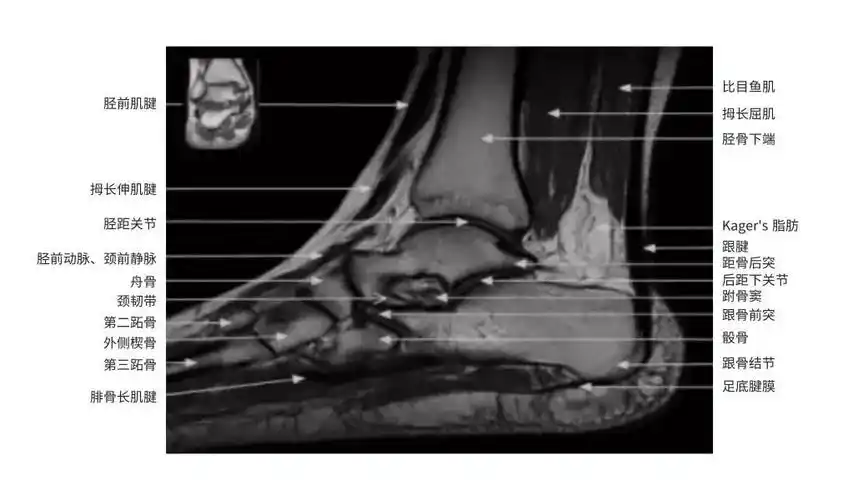

踝关节mri读片要点

踝关节mr断层解剖,解剖变异和病理——第一部分:断层解剖

【影像必备】踝关节mri断层解剖(图文详解)

踝关节mri的断层解剖

【专题】 踝关节正常mri解剖图谱(resonance关节mri解剖之二) [精华]